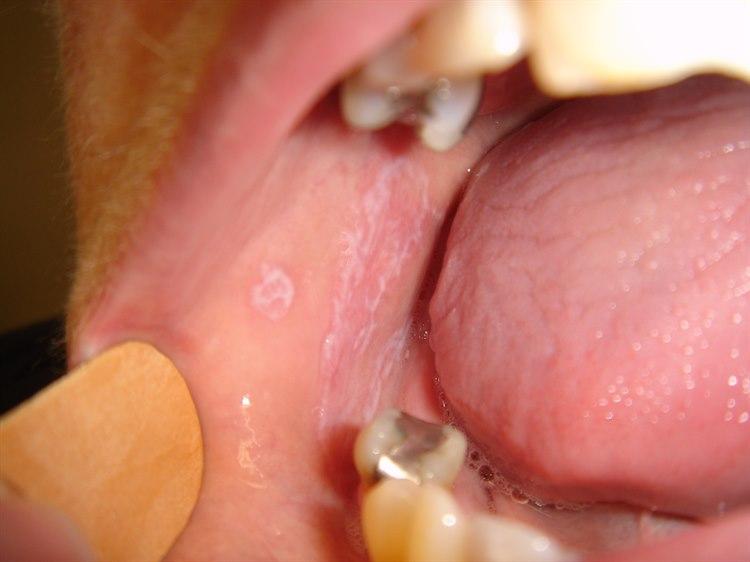

Lichen planus eller lichen ruber planus er en ganske sjelden, langvarig og ofte sterkt kløende hudlidelse som tidlig i forløpet er preget av små, kantete, flate hudforandringer. Hos 25-35 prosent angripes også slimhinner, og dette viser seg hyppigst på innsiden av kinnene der det kan ses hvite flekker og striper (se lichen planus i munnhulen). Typiske steder med hudforandringer er underarmenes håndflateside, lår, legger og området rundt halebeinet/baken.

Lichen planus munnKarakteristiske trekk ved slimhinneforandringer:

- Hvite flekker og striper som kan utvikle seg til områder med sårdannelse

- Slimhinneforandringer kan være eneste tegn

- Ytre kjønnsorganer hos kvinner og penishodet hos menn kan også angripes